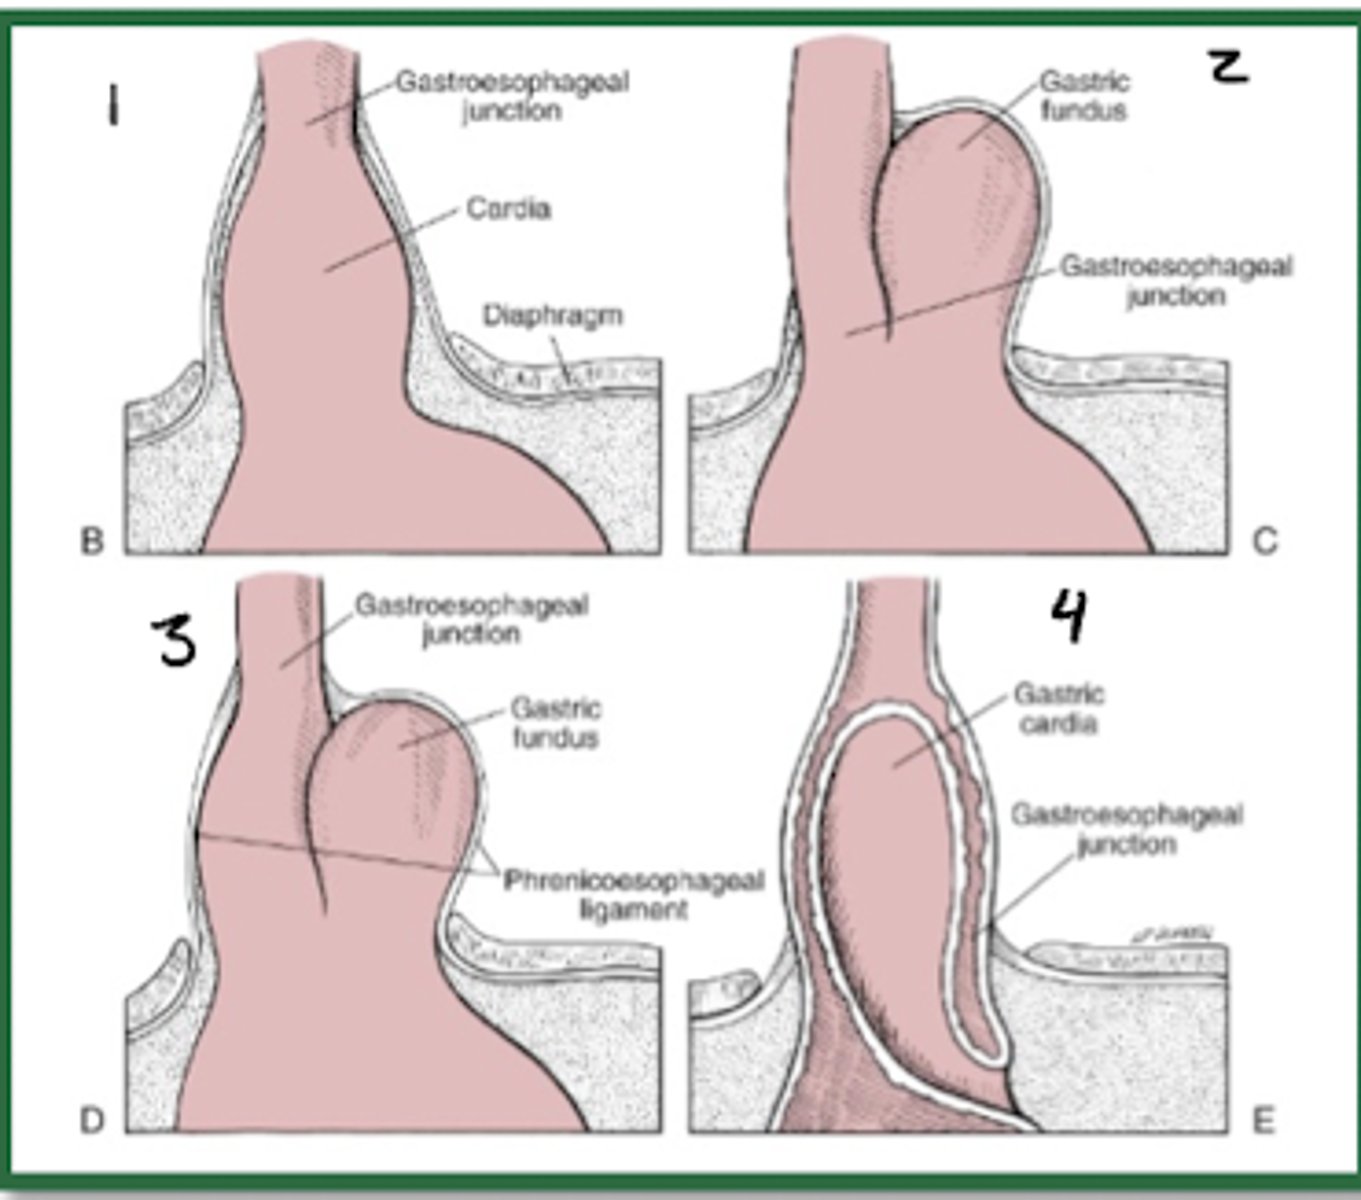

What are the 4 types of hiatal hernias?

•Type I = sliding hiatal hernia

•Types II, III and IV are all subtypes of paraesophageal hernias

45 year old female patient presents with pain in the lower chest after eating. You notice hematemesis. She also appears to have dyspnea and pain on inspiration. You listen to her lungs and note decreased breath sounds. You listen to her abdomen and find bowel sounds on the left chest.

Note that while this patient had signs and symptoms patients are often asymptomatic.

What tests do you order to diagnose this patient?

What do you diagnose this patient with?

How do you treat this patient?

1.) Hiatal Hernia

2) CXR gastric air-fluid level behind cardiac shadow

Upper GI contrast radiography = cephalad displacement of the stomach

Endoscopy demonstrates herniation pattern depending on type

3.) asymptomatic patients don't require treatment. In this case, since the patient is symptomatic, the patient may require surgery through fundoplication techniques